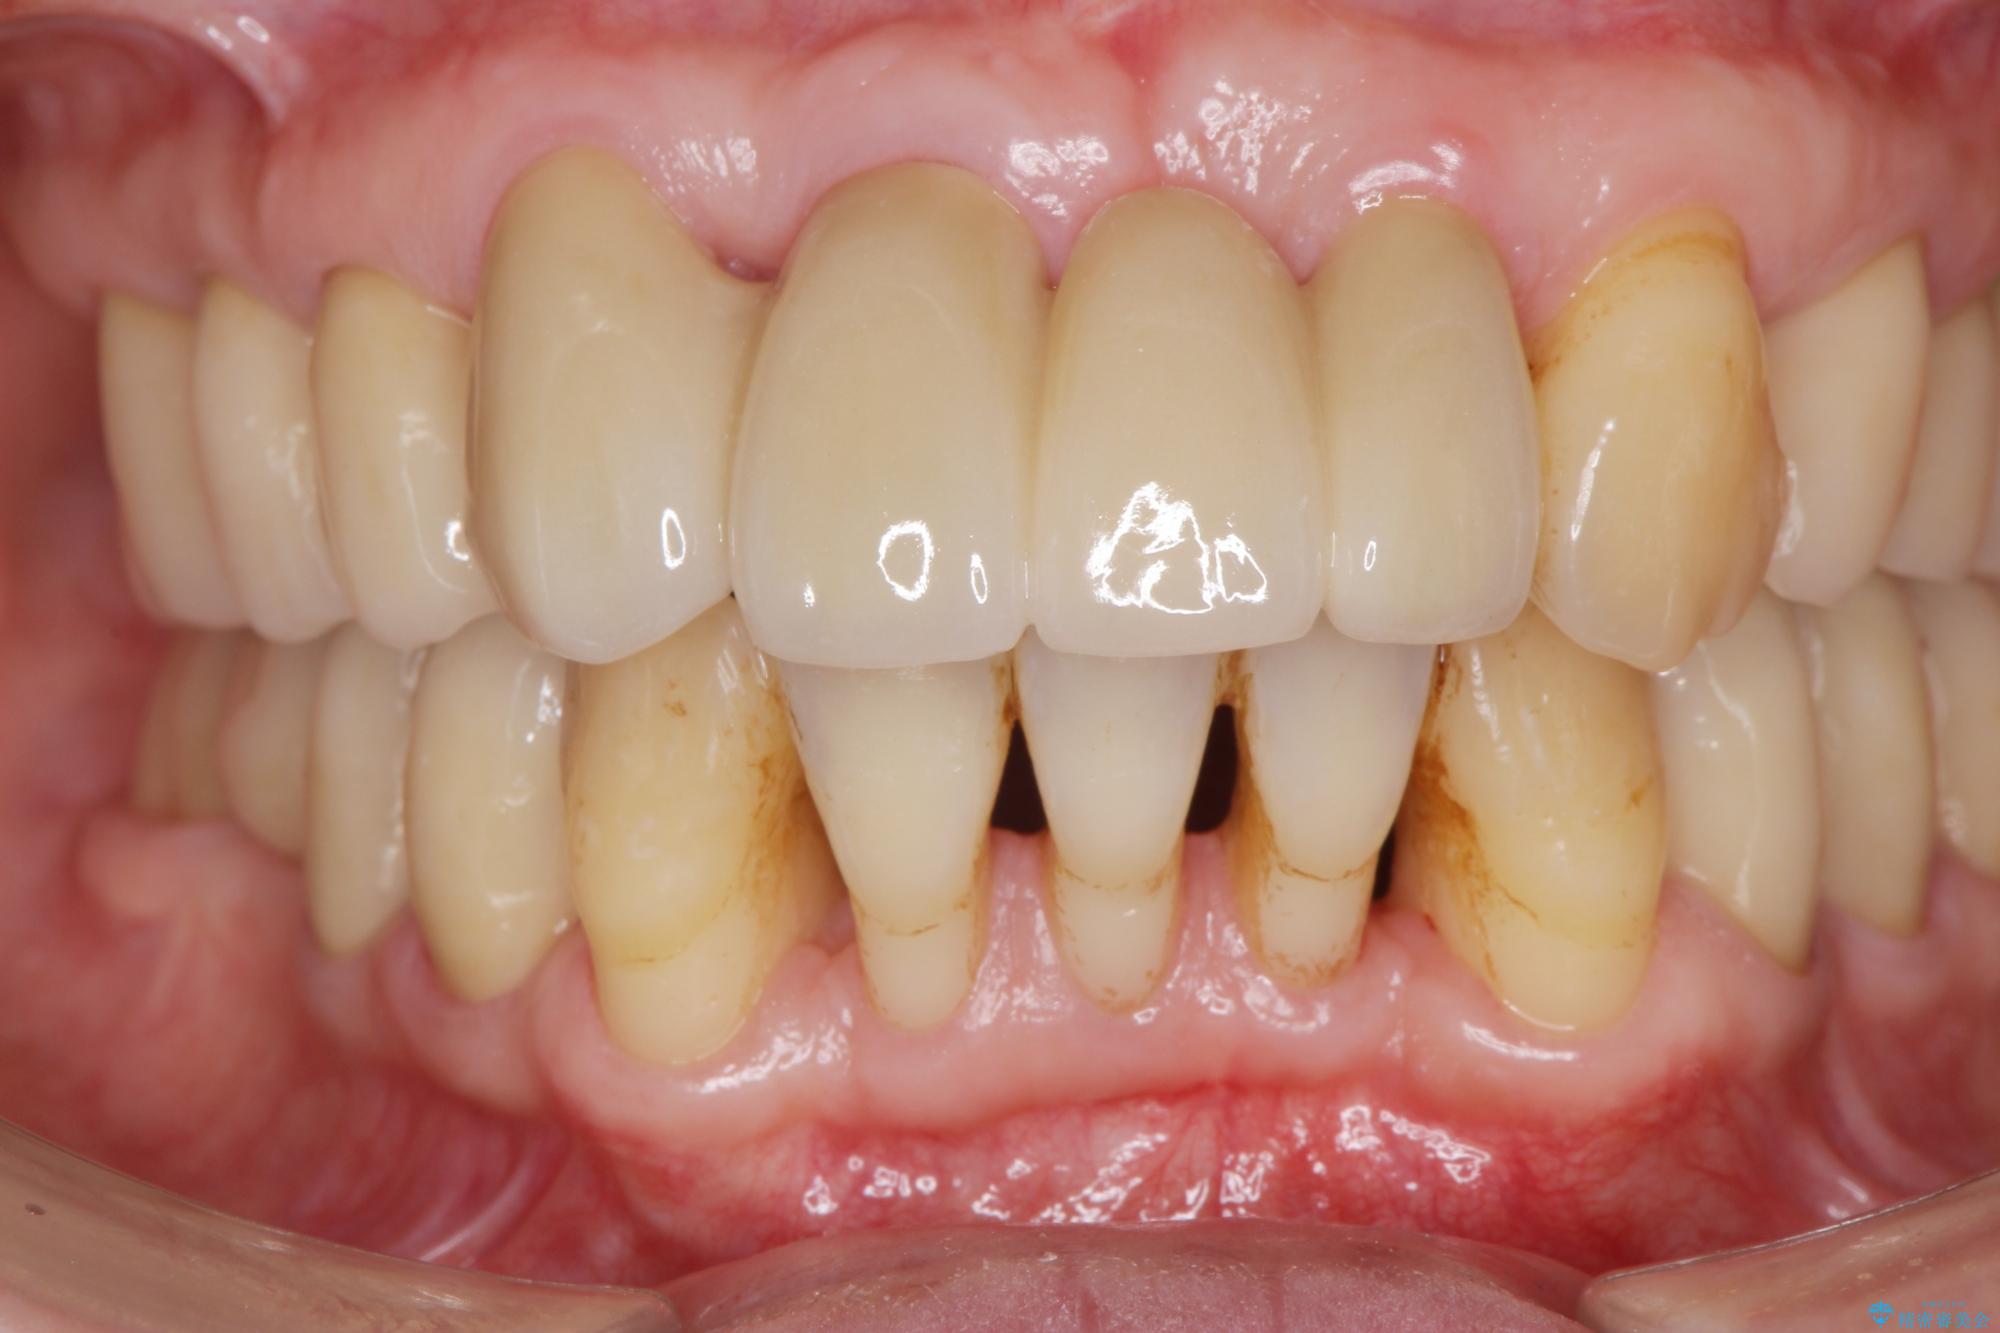

治療後

歯の総合的なマネージメントを行う包括的歯科治療の実践[ 歯周病・矯正・セラミック補綴 ] 治療後画像 歯の総合的なマネージメントを行う包括的歯科治療の実践[ 歯周病・矯正・セラミック補綴 ] 治療後画像 歯の総合的なマネージメントを行う包括的歯科治療の実践[ 歯周病・矯正・セラミック補綴 ] 治療後画像 歯の総合的なマネージメントを行う包括的歯科治療の実践[ 歯周病・矯正・セラミック補綴 ] 治療後画像